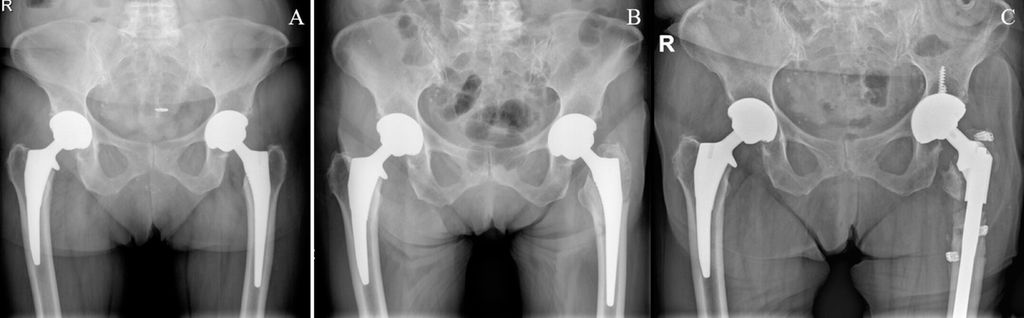

Seit 2015 werden an der Klinischen Abteilung für Orthopädie der Medizinischen Universität Wien nahezu immer zementfreie Schäfte mit Kragen verwendet. Noch nicht publizierte Daten unserer Abteilung zeigen ähnliche Ergebnisse, dass nämlich die Lockerungs- und Frakturrate beim Verwenden der Kragendesigns niedriger ist. Ein demonstratives Beispiel ist in Abbildung 1 zu sehen. Weitere radiologische und Migrationsanalysen werden derzeit vorgenommen.

Abb. 1: (A) Zustand nach beidseitiger zementfreier Hüfttotalendoprothese, rechts Kragendesign, links kragenloses Design; (B) auf der Seite mit kragenlosem Design kommt es zu einer periprothetischen Femurschaftfraktur links; (C) Systemwechsel auf tripolare Pfanne (aufgrund der Mehrfragmentfraktur im Bereich des Trochanter major) und auf einen diaphysär verankernden Schaft